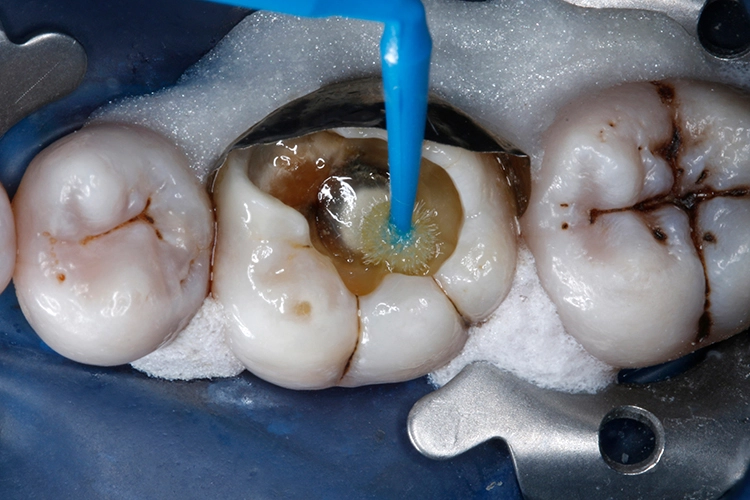

Im nächsten Schritt wurde das thermoviskose Komposit VisCalor (VOCO) im VisCalor Dispenser (VOCO) auf 65 °C erwärmt (Abb. 17). Die schmale, biegsame Kanüle der VisCalor Kompule erleichtert eine direkte Applikation auch in schwer zugängliche Bereiche und enge Kavitätenareale (Abb. 18). Die Kavität wurde mit dem ersten 2-mm-Inkrement bis ca. zur Hälfte der Defekthöhe aufgefüllt.

Durch die niedrigviskose Konsistenz im erwärmten Zustand resultiert ein hervorragendes Anfließverhalten an die Kavitätenwände (Abb. 19). Die 1. Kompositschicht wurde für 10 Sek. mit einer Polymerisationslampe (Lichtintensität ≥ 1.000 mW/cm²) ausgehärtet (Abb. 20).